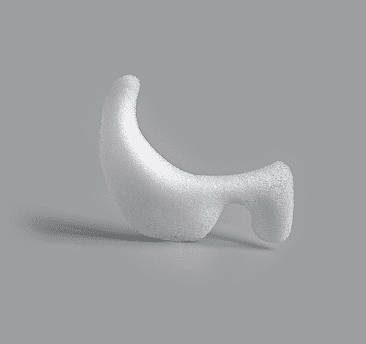

AIRO Implnat